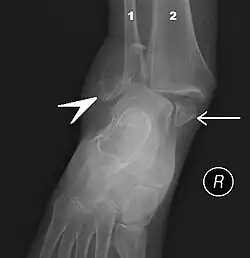

| Fracture of both sides of the ankle with dislocation as seen on anteroposterior X-ray. (1) fibula, (2) tibia, (arrow) medial malleolus, (arrowhead) lateral malleolus | |

On X-rays, there can be a fracture of the medial malleolus, the lateral malleolus, and/or of the anterior/posterior margin of the distal tibia. The posterior margin (known as the posterior malleolus) is much more frequently injured than the anterior aspect of the distal tibia. If both the lateral and medial malleoli are broken, this is called a bimalleolar fracture (some of them are called Pott's fractures). If the posterior malleolus is also fractured, this is called a trimalleolar fracture.